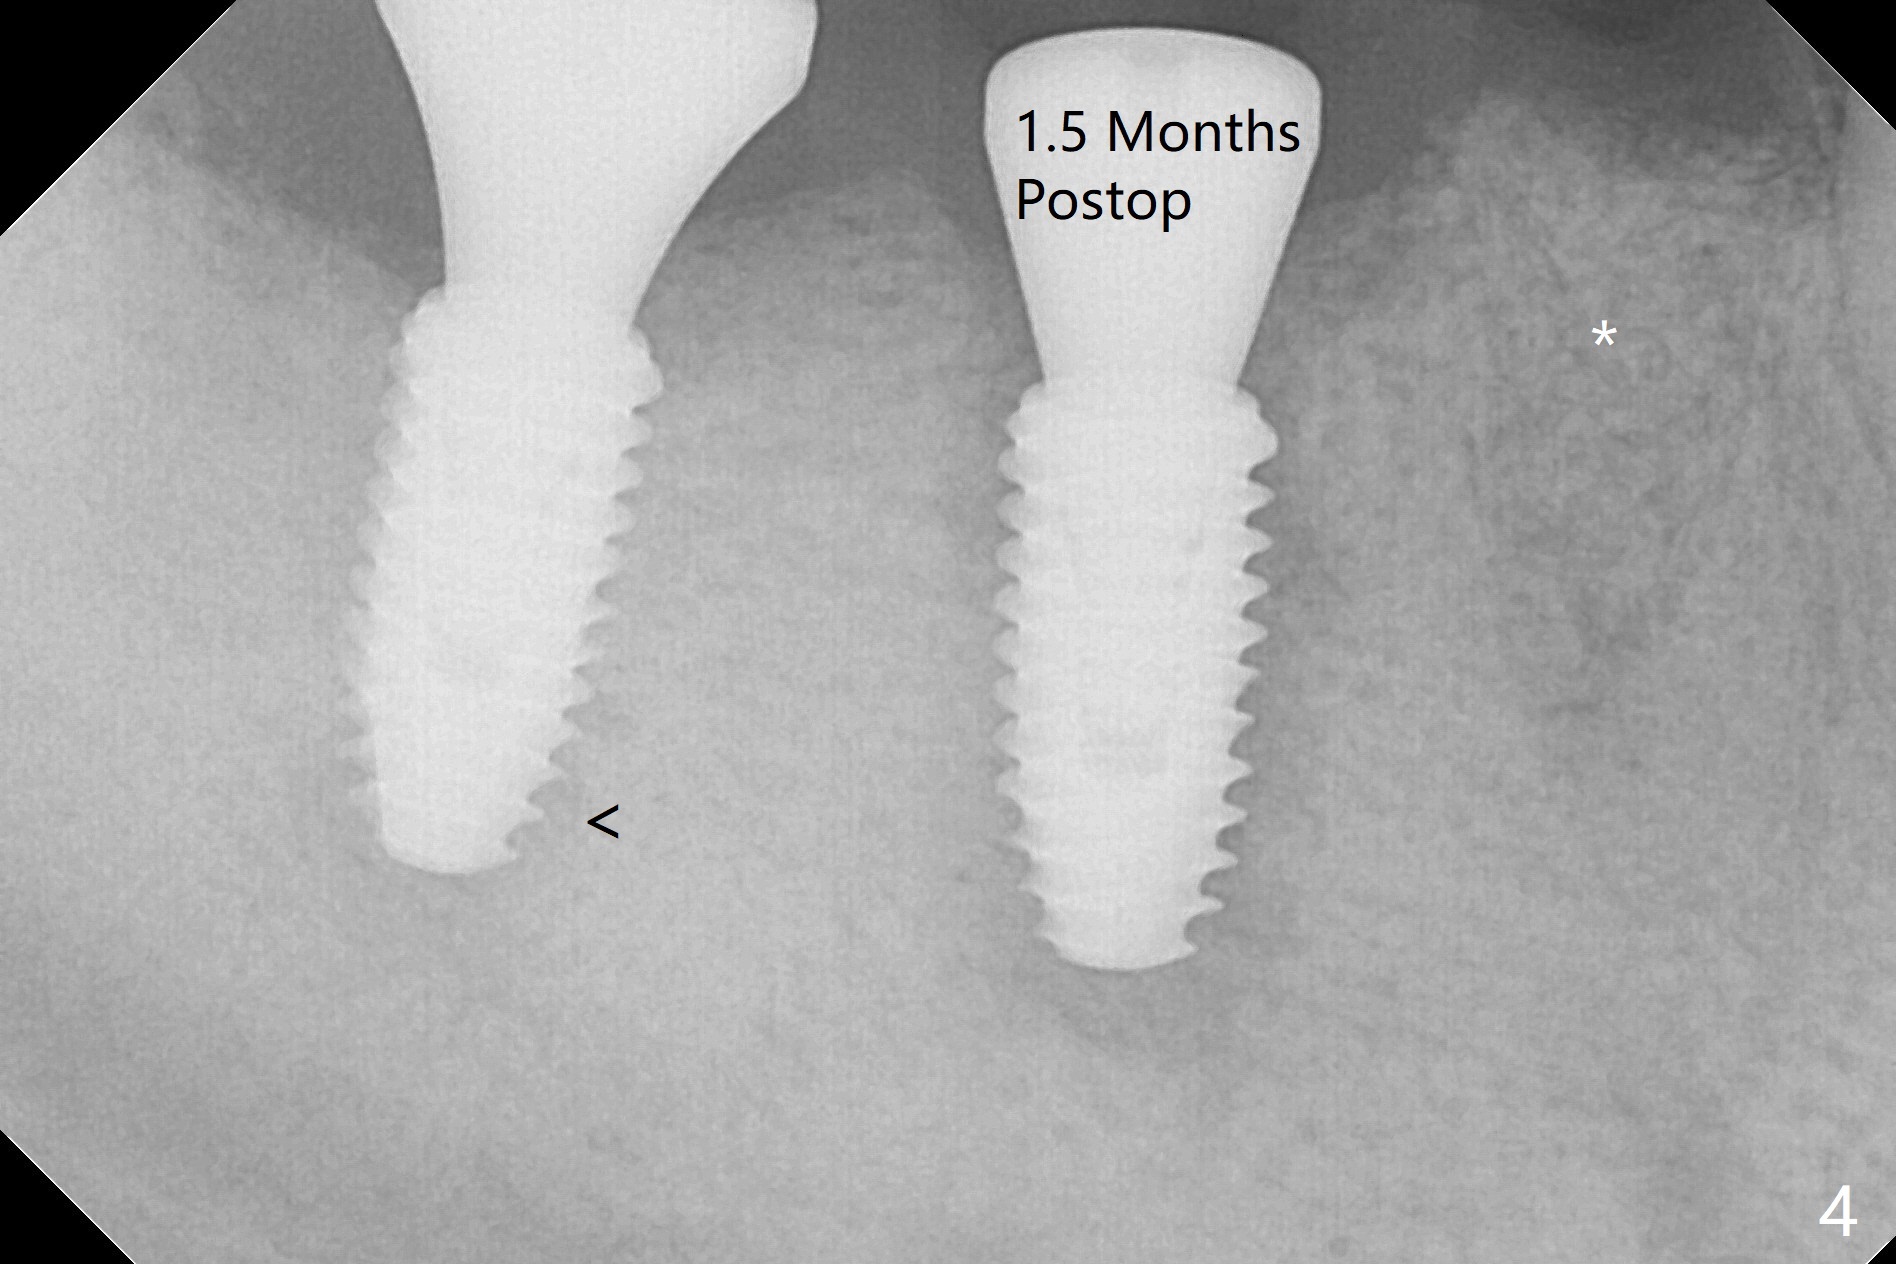

The patient is hesitant about apicoectomy.  After discussion of advantages and disadvantages of the latter vs. extraction and implant, the patient chooses the extraction.  The latter turns out to be smooth with socket preservation (Fig.5, 6 *).  Immediately postop PA shows bone loss at #30 and minor degree around the apex of #31 implant (Fig.4 <), which is related with hard bone and bone necrosis due to heat.